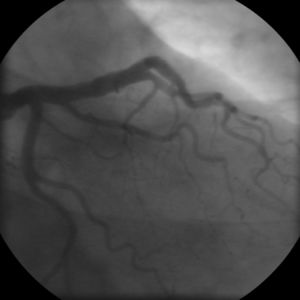

يمكن اعتبار مرض تصلب شرايين القلب مجموعة من الأمراض التي تصيب القلب. واحدة من هذه صور هذا المرض هو شخص بلا أعراض وجدران شرايين قلبه التاجية مبطنة من الداخل بخطوط من الدهون atheromatous streaks. يمثل ظهور هذه الخطوط المرحلة الأولى من مرض القلب التاجي ولكنها لا تعيق تدفق الدم خلال الشريان. إذا تم عمل تصوير الشرايين التاجية Coronary Angiogram خلال هذه المرحلة من المرض فانه من المحتمل ألا يظهر أي دليل على وجود مرض تصلب الشرايين القلبية وذلك لان قطر تجويف الشريان لم يقل. خلال عدة سنوات، تزداد هذه الخطوط الدهنية سماكة، وازدياد سماكتها مبطِنة جدار الشريان يؤدي في النهاية إلى صغر تجويفه وبالتالي يعوق مسار الدم خلاله. اُعتقد في السابق أن عملية تكوّن الصفائح الدهنية عملية بطيئة وتدريجية، لكن ظهرت دلائل حديثة على أن التكون التدريجي لهذه الصفائح يُسرّعُه تمزقات صغيرة تحدث فيها مما يؤدي إلى ازدياد حجم الصفيحة الدهنية نتيجة تراكم المواد المتخثرة عليها. من النادر أن تسبب الصفائح الدهنية التي تسد أقل من 70 في المائة من تجويف الشريان أعراض مرض انسداد الشرايين التاجية. في حال ازدياد حجم الصفيحة مسببة انسداد الشريان بنسبة تزيد عن 70 في المائة، تظهر في الشخص في هذه المرحلة أعراض انسداد الشرايين التاجية. يمكن القول في هذه المرحلة من المرض أن الشخص لديه مرض نقص التروية القلبية ischemic heart disease. تُلاحظ أولى أعراض مرض نقص التروية القلبية خلال الأوقات التي يزيد فيها الضغط على عمل القلب. كمثال على ذلك، الم الذبحة الصدرية الجُهدية exertional angina أو تراجع قدرته على تحمل التمارين البدنية. قد يتطور المرض فيما بعد ليصل إلى الحد الذي يُسد فيه تجويف الوعاء الدموي بشكل شبه كامل، معيقاً وصول الدم حامل الأكسجين إلى عضلة القلب. المصابون بهذه الدرجة من مرض الشريان التاجي يكونون قد عانوا من جلطة قلبية (ذبحة صدرية) مرة أو اثنتان، وقد يكون لديهم أعراض أو علامات مرض الشريان التاجي المزمن، متضمنا الم الذبحة الصدرية بدون أي مجهود بدني angina at rest أو الاستسقاء الرئويflash pulmonary edema. يجب أن يتم التمييز بين كلٍ من مرض نقص التروية القلبية myocardial ischemia والجلطة القلبية (احتشاء عضلة القلب) myocardial infarction. نقص التروية معناه أن كمية الأكسجين التي تصل إلى عضلة القلب غير كافية لتلبية احتياجه. عندما تنقص تروية عضلة القلب فإنها لا تعمل بالشكل الأمثل، وإذا نقصت التروية لمساحة كبيرة من عضلة القلب فان ذلك قد يؤدي إلى عدم قدرة العضلة على الانقباض والانبساط. إذا تحسن تدفق الدم إلى العضلة فان نقص التروية يمكن عكسه. بينما الجلطة القلبية معناها أن نسيج العضلة قد مات ولا يمكن عكس ذلك لقلة تدفق الدم المشبع بالأكسجين إليها. قد يحدث للشخص تمزق للصفيحة الدهنية في أي مرحلة من مراحل المرض. التمزق المفاجئ للصفيحة قد يؤدي إلى جلطة قلبية مفاجِئة (ذبحة صدرية).

- Coronary angiography

In "stable" angina, chest pain with typical features occurring at predictable levels of exertion, various forms of cardiac stress tests may be used to induce both symptoms and detect changes by way of electrocardiography (using an ECG), echocardiography (using ultrasound of the heart) or scintigraphy (using uptake of radionuclide by the heart muscle). If part of the heart seems to receive an insufficient blood supply, coronary angiography may be used to identify stenosis of the coronary arteries and suitability for angioplasty or bypass surgery.[17]